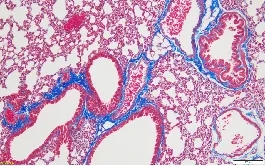

04.Masson染色